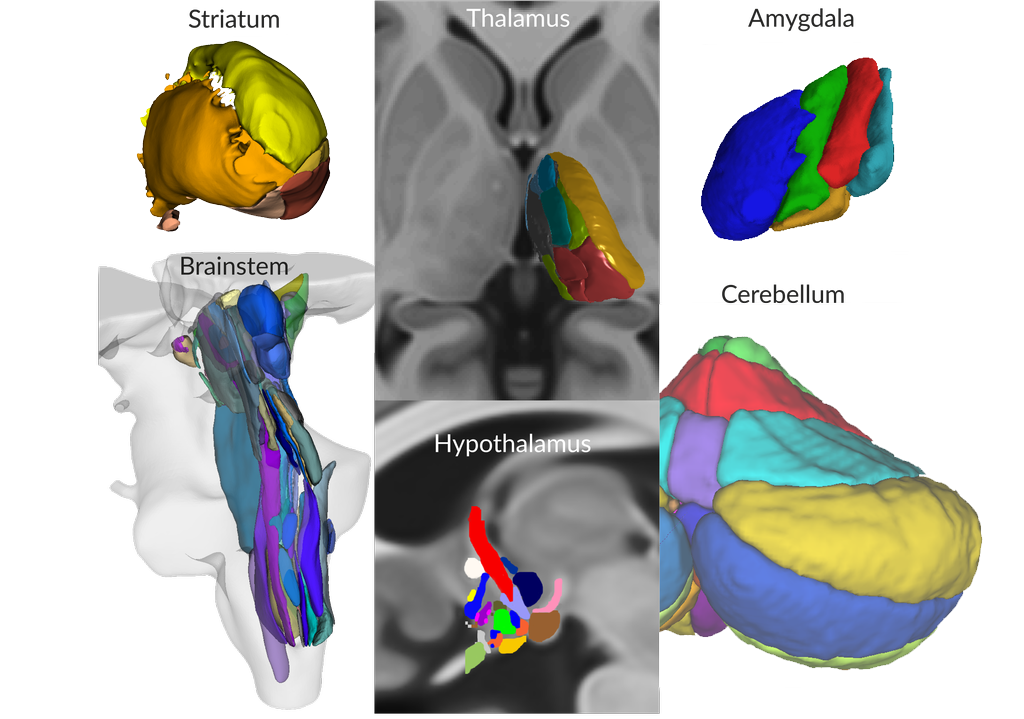

It is not all about Cortex

also Subcortex and Brainstem are presented in meticulous Detail

Each drawing in the atlas shows the delineation of individual anatomical structures representing their cross-sectional area of the corresponding 3D model.